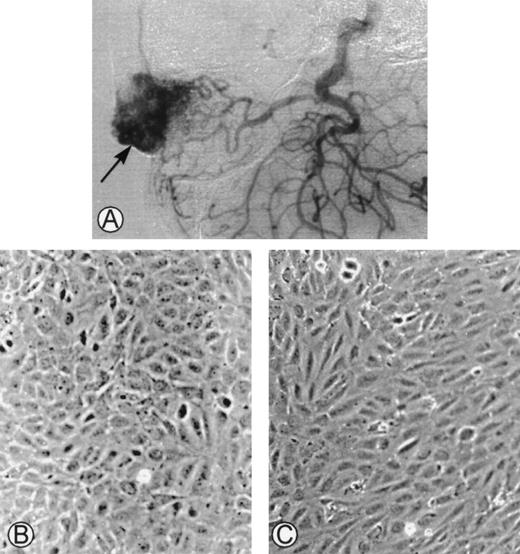

This study was conducted in accordance with the principles of the Declaration of Helsinki and the 1975 Declaration of Tokyo. Surgical excisions were performed in 11 consecutive patients with arteriovenous malformations, and samples were collected (Fig1A). Cells were successfully cultured from the surgical biopsies of 6 patients. Because a limited number of cells grew in culture, a complete characterization could only be achieved in 4 cases. In the other 5 cases, the tissues were either necrotic after embolization, infected, or did not grow in in vitro conditions. The main clinical features of the patients are summarized in Table1. The hemostatic parameters were normal and there was no evidence of intravascular coagulation.

(A) Angiogram of one of the cephalic arteriovenous malformations. The vascular tumor was embolized using an endovascular technique and was operated on. The specimen was used as starting material to obtain endothelial cells derived from the malformation. (B) Phase-contrast microphotographs of confluent HUVEC or (C) confluent AMEC grown on gelatin-coated plastic dishes (original magnification ×100).

Morphological Aspect

The initial culture from surgical pieces of arteriovenous malformations (Fig 1A) contained heterogeneous populations. Only cultured cells that had the morphological characteristics of endothelial cells were kept. At confluence, HUVEC had a cobblestone aspect when cultured on gelatin-coated plastic dishes with a strict monolayer growth (Fig 1B). At confluence, AMEC cultured on gelatin-coated plastic dishes had an elongated form with an endothelial-like polygonal morphology. They were closely contiguous and grew as a monolayer (Fig 1C).